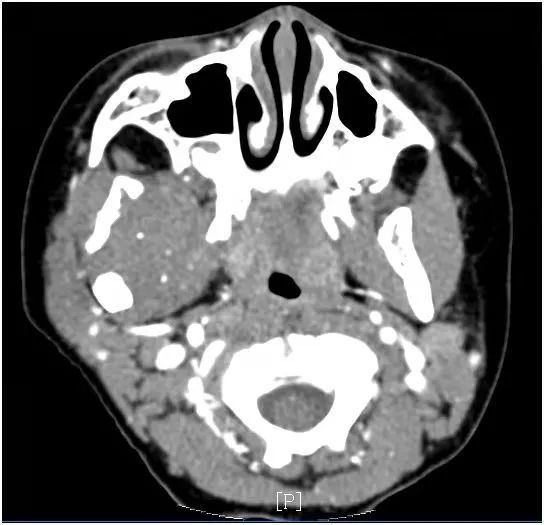

外院ct和核磁检查,发现张不开嘴是因为支配张口的“翼内肌”和“翼外肌”以及“颞下颌关节”受到了肿瘤侵犯。转至上海市儿童医院耳鼻喉科就诊后,最终确诊为翼腭窝肿瘤侵犯上述张口肌肉和关节。翼腭窝是由上颌骨后壁、蝶骨翼突及颚骨垂直板这些骨性结构围成的狭小空间。乐乐的翼腭窝肿瘤侵不仅损伤了颞下颌关节,还侵犯了附着于蝶骨翼突的翼外肌和翼内肌这两组控制张嘴的肌肉,才导致了他饭来难张口。要彻底根治必须将其切除。

翼腭窝血管神经丰富,是侧颅底的“交通要道”,术中极易损伤面部的运动和感觉神经以及颅底重要结构造成不可逆的功能损害。根治手术之前的内镜下活检提示乐乐的肿瘤系侵袭性纤维瘤,侵袭性纤维瘤虽非恶性,不会远处转移,但是局部侵袭能力一点也不亚于恶性肿瘤,又对放化疗不敏感,使得手术彻底切除成为唯一的治疗方法。但是翼腭窝的位置隐蔽又有较多重要神经血管,对手术的完整切除及术中功能保护提出了极高要求。手术由李晓艳主任医师主刀,经患儿右侧耳前切口腮腺前缘入路,在丰富的血管神经尤其是面神经的细小分支之间游刃穿梭。最终,从右侧上颌骨后缘及右侧颧弓间的间隙进入右侧翼腭窝。在保护好翼腭窝重要神经血管的基础上,经内窥镜引导下,李主任将肿物逐步分离并完整切除。术后病理明确了侵袭性纤维瘤的诊断,孩子术后恢复良好且面部神经功能完好,张口受限改善,目前已顺利康复出院。